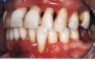

ist der landläufige Begriff für Zahnfleischentzündungen. Der Patient bemerkt meistens, daß das Zahnfleisch blutet oder daß die Zähne länger als früher aussehen.

Entzündungen durch Beläge